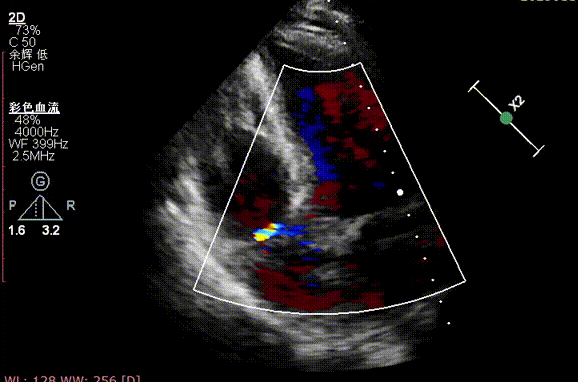

术前超声

术后超声

超声心动图提示:主动脉瓣脱垂并重度关闭不全,二尖瓣脱垂并中-重度关闭不全,左心增大,升主动脉轻宽,三尖瓣中度反流。EF:55%。

术中经股动脉切开建立血管通路,患者为单纯反流患者,无明显钙化,无需球囊预扩张,术中建立轨道后直接将输送器送入主动脉瓣目标位置,轻松实现定位件的正确入窦,后成功释放28mm瓣膜。经DSA造影和超声等综合评估显示瓣膜释放位置完美,瓣膜工作稳定,术后即刻主动脉瓣反流消失,人工主动脉瓣瓣环内无反流,无瓣周漏,患者临床症状和血流动力学明显改善。